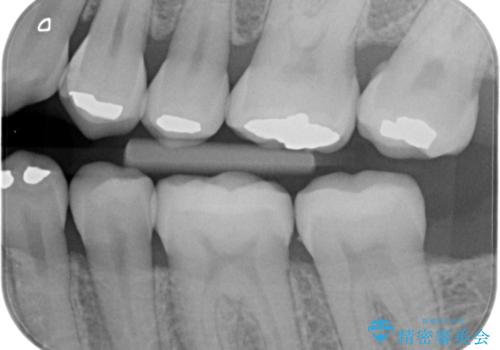

アマルガムを除去 虫歯を除去して、セラミックのつめものに

- 劣化したプラスチックとアマルガムをはずしてセラミックにしていく治療を行いました。

アマルガムは水銀が含まれている為、外したい方が増えています。

- 左下6番、左下7番 セラミックインレー 7.7万円×2本費用は治療当時の料金となります

①初回 アマルガム、古い詰め物の除去、虫歯の除去

裏打ちをしく、インレーの形として整える、シリコンを使用した歯型とり

仮の詰め物でお帰り頂きます。

②2回目 製作したセラミックインレーの接着